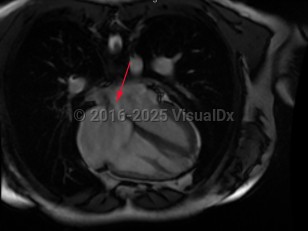

Atrial septal defect

The presence of a defect (opening) in the septum that separates the 2 atria of the heart with resultant flow. It can be congenital or acquired. Associated clinical issues may include flow of oxygenated blood from the left atrium to the right atrium, producing a volume overload on the right heart; flow of unoxygenated blood from the right atrium to the left atrium resulting in cyanosis; and/or traverse of emboli from the venous circulation to systemic circulation, causing a stroke, transient ischemic attack, or other embolic events.